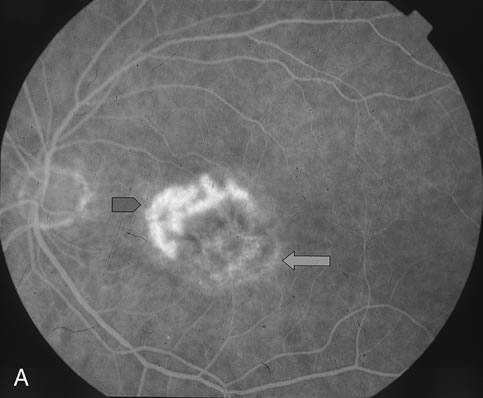

The classic and occult components of CNV are outlined in Figure 2. The percent of the CNV that is classic can then be determined as a proportion of the total CNV. In Figure 2A and B, the area of classic CNV measures 978 square microns and the total lesion measures 11,180 square microns. The classic component is thus 9% of the entire CNV and this lesion is classified as “minimally classic” CNV (defined as less than 50% classic CNV).23,40 The fluorescein angiogram demonstrates another mixed classic and occult CNV lesion in Figure 3. Using digital area measurements, the lesion in Figures 3A and B is composed of 79% classic CNV and fulfils the criteria for predominantly classic, subfoveal CNV that may benefit from verteporfin-PDT based on TAP findings.23,40 The TAP studies also demonstrated a visual benefit in eyes that had prior nonfoveal, thermal laser photocoagulation and subsequent recurrence of CNV below the fovea.23,40 In Figure 4A, subfoveal CNV recurrence in an eye with prior thermal photocoagulation is demonstrated. One month following verteporfin-PDT treatment, Figures 4B (early phase) and 4C (late phase) demonstrate characteristic hypofluorescence of the treated subfoveal CNV on fluorescein angiography.

Fig. 4. A. Mid-phase FA (1:23) demonstrates subfoveal hyperfluorescence corresponding to recurrent CNV (blue arrowhead) adjacent to an area previously treated with thermal photocoagulation (green arrow). B. Early-phase FA (28 seconds) 4 weeks status-post verteporfin-PDT demonstrates hypofluorescence (blue arrowhead) corresponding to the PDT treated area of recurrent CNV. C. Late-phase FA (3:40) 4 weeks status-post verteporfin-PDT demonstrates fluorescein staining in the area of prior thermal laser photocoagulation. There is a small rim of fluorescein staining around an area of hypofluorescence corresponding to the verteporfin-PDT treated area of recurrent CNV (blue arrowhead).